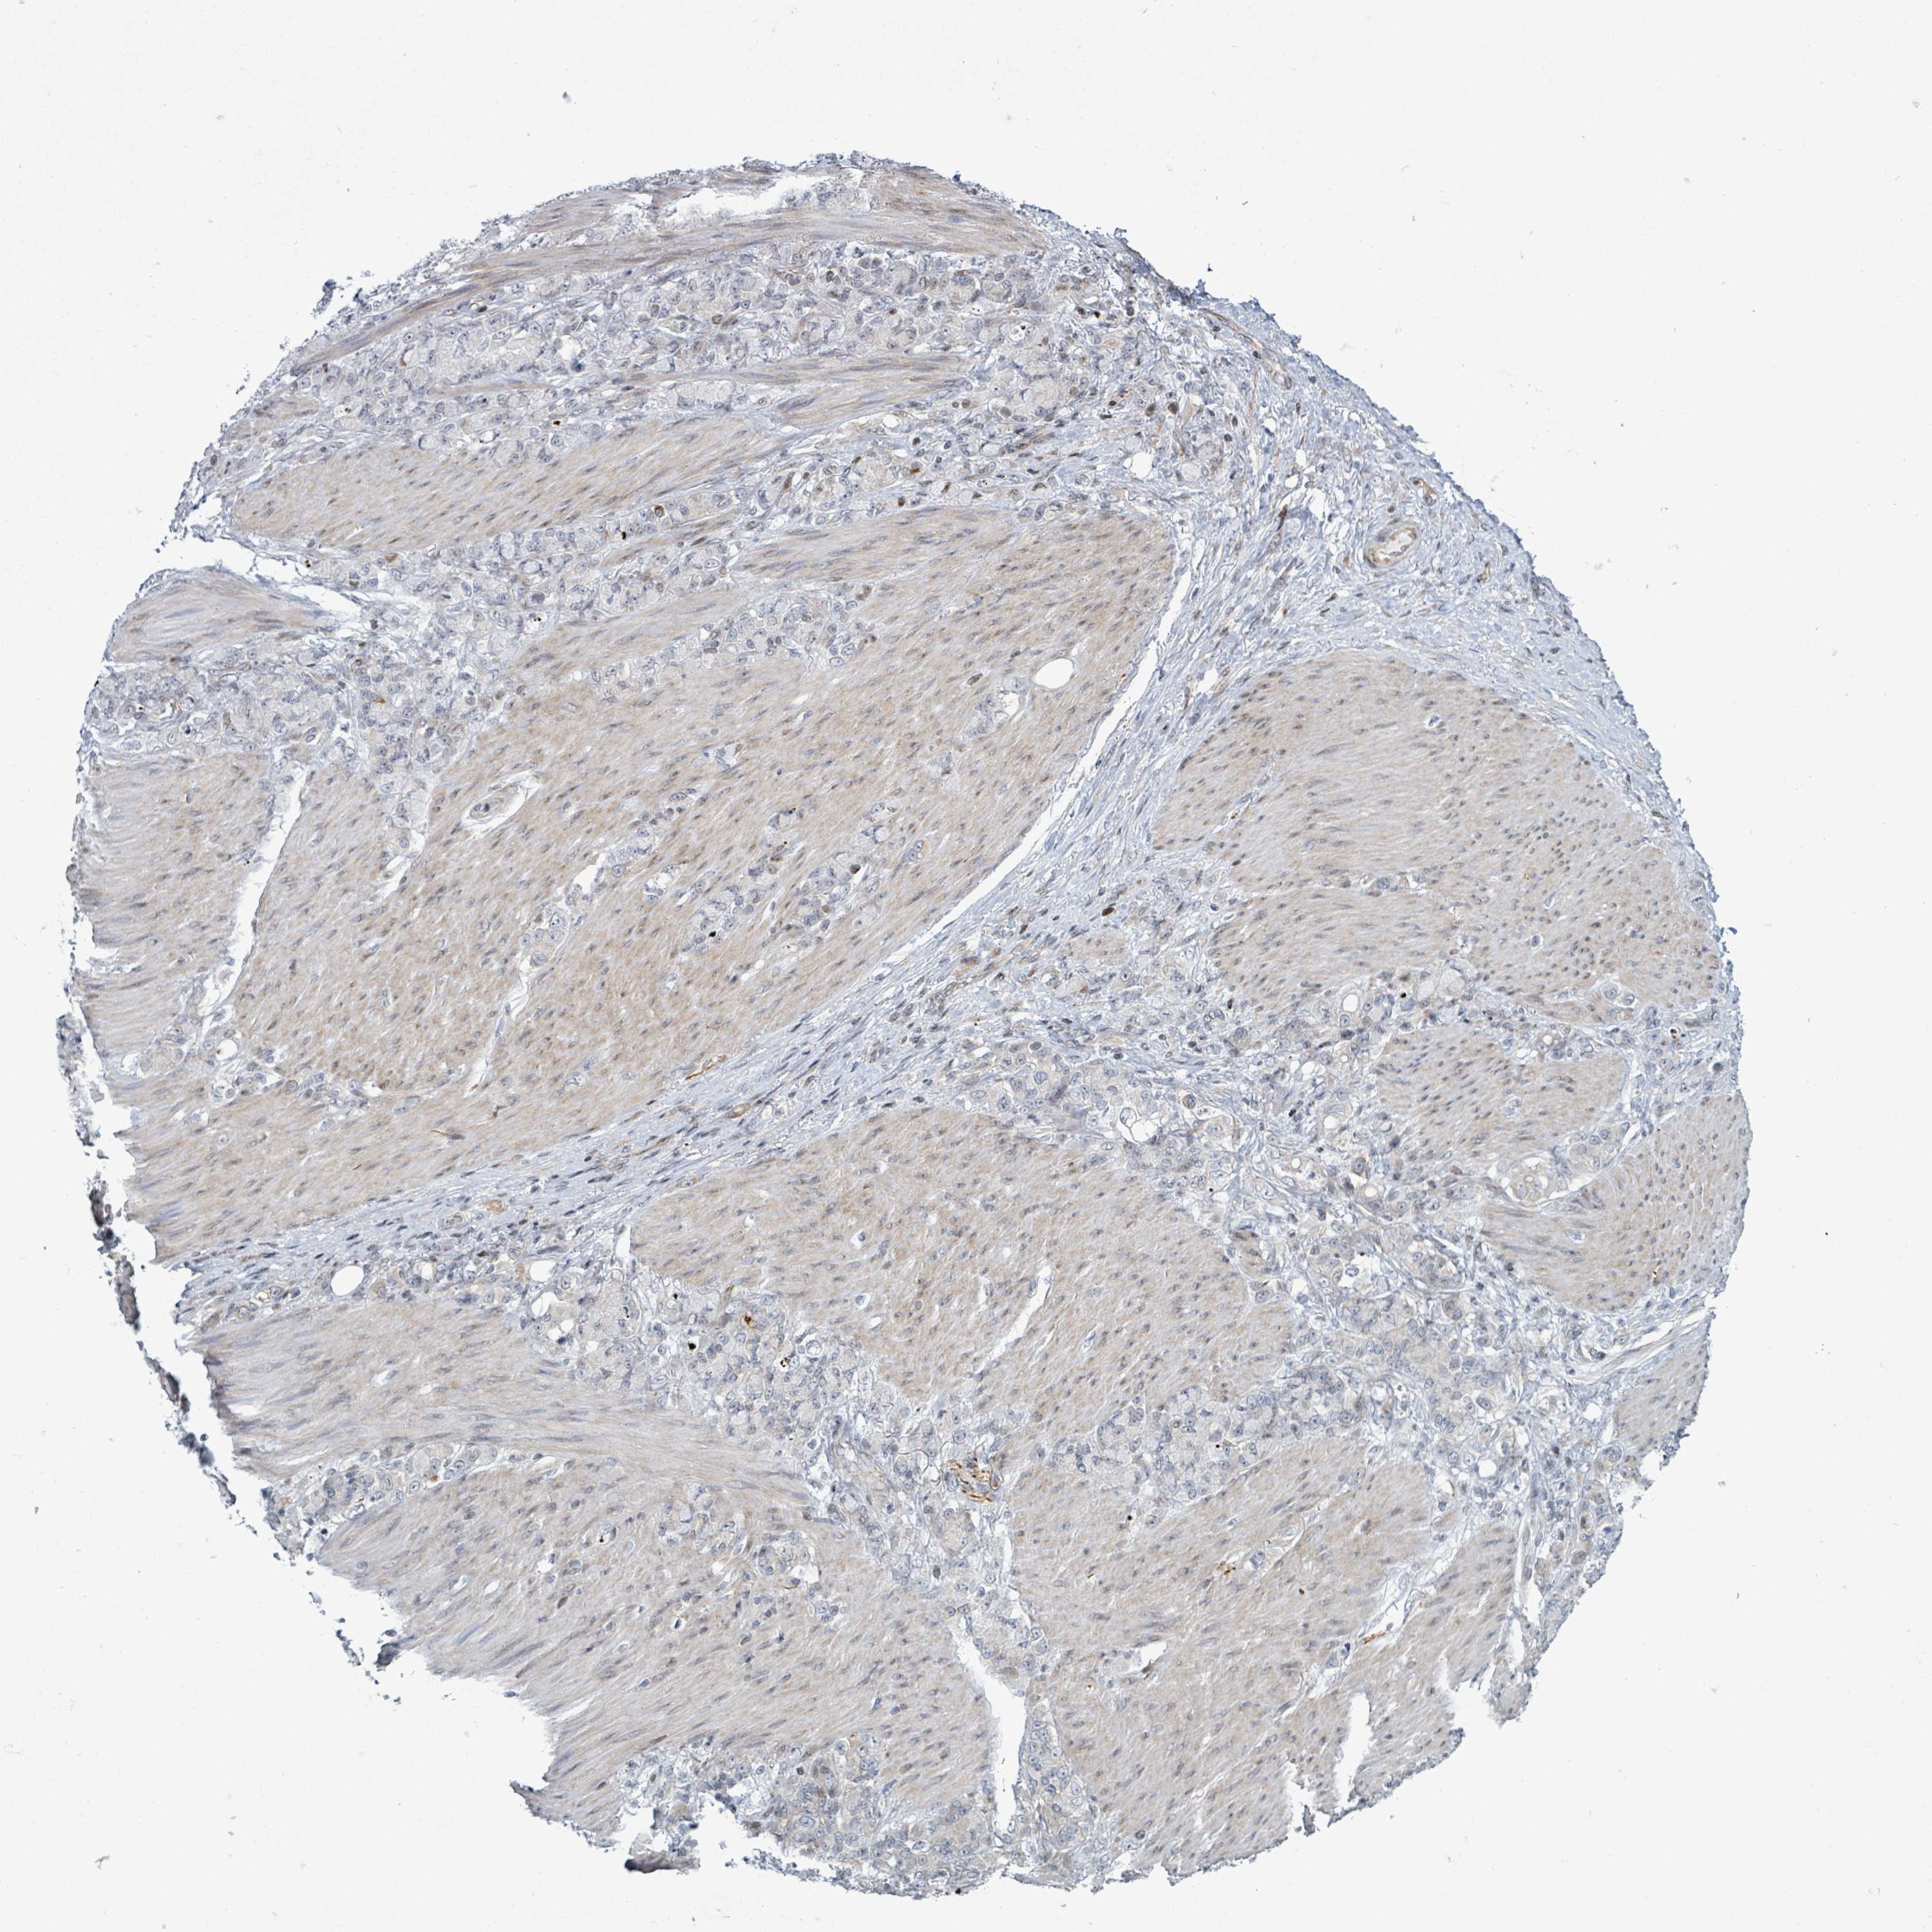

STOMACH CANCER - Protein expressioni

A mouse-over function shows sample information and annotation data. Click on an image to view it in a full screen mode. Samples can be filtered based on level of antibody staining by selecting one or several of the following categories: high, medium, low and not detected. The assay and annotation is described here.

Note that samples used for immunohistochemistry by the Human Protein Atlas do not correspond to samples in the TCGA dataset.

Antibody stainingi

Antibody staining in the annotated cell types in the current human tissue is reported as not detected, low, medium, or high, based on conventional immunohistochemistry profiling in selected tissues. This score is based on the combination of the staining intensity and fraction of stained cells.

Each image is clickable and will lead to virtual microscopy that enables deeper exploration of all samples and also displays staining intensity scores, fraction scores and subcellular localization as well as patient and tissue information for each sample.

Antibody HPA051804

Antibody HPA063581

Staining

High

Medium

Low

Not detected

Intensity

Strong

Moderate

Weak

Negative

Quantity

>75%

75%-25%

<25%

None

Location

Nuclear

Cytoplasmic/membranous

Cytoplasmic/membranous,nuclear

Adenocarcinoma, NOS